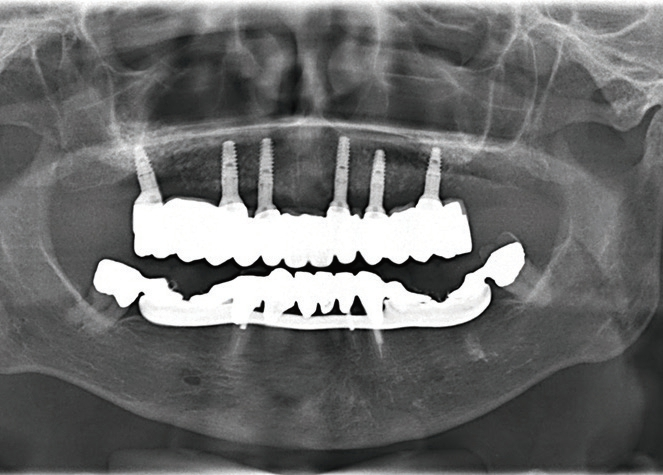

Für eine ausreichende Abdeckung der eingebrachten Implantate jeweils palatinal und vestibulär und Sicherstellung der Nutrition der Knochenlamellen ist eine Mindestbreite des Knochens von 2 bis 3 mm erforderlich. Für die Durchführung des Bone Splittings ist es notwendig, eine relativ tiefe Osteotomie des Kieferkamms zu erreichen. Dies kann heute entweder mit oszillierenden Sägen oder auch mit Hochleistungs- Piezochirurgiegeräten erfolgen [8] (Abb. 3). Bei der Anwendung der Piezochirurgie im Vergleich zur oszillierenden Säge kann die Präparation schonend erfolgen, gerade dann, wenn die Behandlung nicht in Intubationsnarkose erfolgt. Auch bei der Präparation eines Mukoperiostlappens ist es anzustreben, dass es zu keiner kompletten Loslösung des mobilisierten Knochensegmentes kommt. Diese sollte auch in der Basis weiterhin am Knochen fixiert sein und lediglich im Sinne einer Grünholzfraktur mobilisiert werden. Nach der Implantatinsertion wird der Spaltraum mit eventuell anfallenden Knochenspänen und Kollagenfleece oder auch mit einem resorbierbaren Knochenersatzmaterial aufgefüllt. Bei reduziertem vertikalen Knochenangebot im posterioren Bereich und der Notwendigkeit einer Sinusbodenelevation sollte dann die Osteotomielinie für das Bone Splitting nicht fortgeführt werden, da sonst keine ausreichende Primärstabilität für die Implantate erreicht werden kann (Abb. 4).

Durch das Bone Splitting ist die Anwendung von 3DBohrschablonen stark eingeschränkt, da das Knochenlager erst durch die Aufdehnung letztendlich genau bestimmt werden kann. Daher kann es auch zu Abweichungen der Implantatposition von der optimalen Positionierung kommen [15]. Dies stellt dann im weiteren Verlauf hohe Anforderungen an den Zahntechniker und prothetisch tätigen Kollegen, damit eine suffiziente prothetische Versorgung erreicht werden kann. Oftmals wird deshalb bei einem Bone Splitting auf eine festsitzende Versorgung verzichtet, um die ungünstige Implantatpositionierung durch eine Stegversorgung zu kompensieren. Da heutzutage die Insertion von angulierten Implantaten zur Vermeidung einer Sinusbodenelevation prothetisch etabliert ist, stehen aber weitere Bauteile zur Verfügung, die es gerade bei einem Bone Splitting mit einer geringen apikalen Basis erlauben, die Achsdivergenzen auszugleichen [3].

Nach einer initialen Abformung können vom Zahntechniker die optimalen Aufbauten nach der physiologischen Aufstellung und Wachseinprobe ausgewählt werden (Abb. 7 bis 9). Diese werden dann in die Implantate eingeschraubt und verbleiben dort, ohne dass sie wieder entnommen werden. Durch die Auswahl der Aufbauten vom Zahntechniker kann dort auch gleich eine Verblockung vorbereitet werden, mit der es möglich ist, die endgültig erreichte Position der angulierten Aufbauten direkt in das Labor zu übertragen. Somit stellt das Meistermodell eine identische Kopie der klinischen Situation dar. Dies ist notwendig, damit im Rahmen von CAD/CAM-Verfahren Gerüste für die weitere prothetische Versorgung gefräst werden [14]. Je nach Umsetzung der patientenindividuellen Aufstellung kann die definitive Versorgung hergestellt werden. Dort bestehen heute die Möglichkeiten der CAD/CAM-Technologien mit einem Titan- oder einem Keramikgerüst zur Verfügung. Sofern sich kein absolut passgenaues Gerüst erreichen lässt, kann dies durch eine Klebebasis kompensiert werden [5]. Dies wird in der Regel bei reinen Zirkonoxidgerüsten erforderlich. Im weiteren Ablauf kann die individuelle Charakterisierung der Vestibulärflächen und des Weichgewebsübergang erreicht werden (Abb. 10 bis 14).